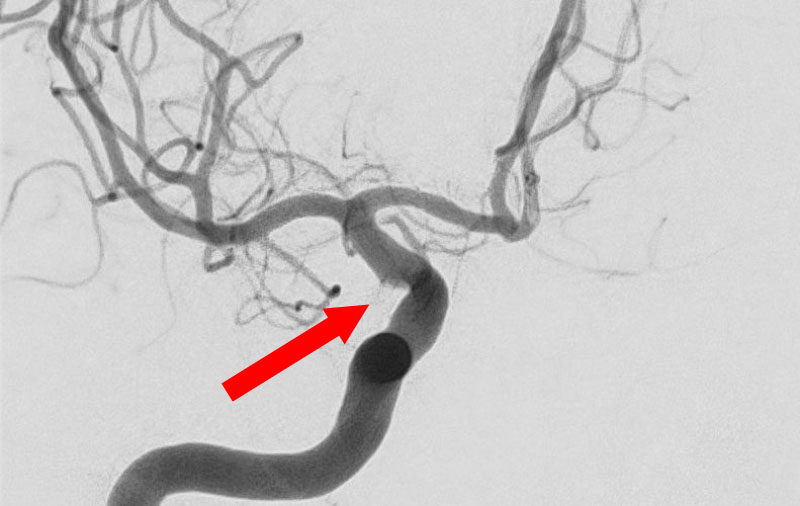

No.1596 手術前